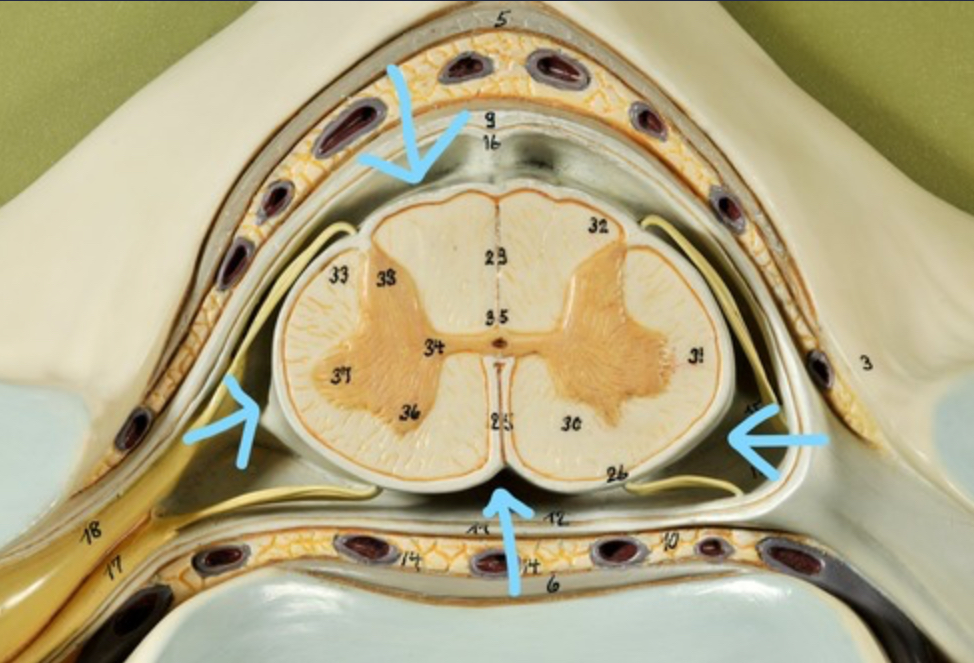

Dura mater (outermost layer)

White matter of spinal cord

Gray matter of spinal cord

Ventral horns (of gray matter)

Lateral horns

Dorsal horns

Anterior columns of white matter

Lateral columns of white matter

Posterior columns of white matter

central canal of spinal cord

Pia matter

Subarachnoid space

Arachnoid matter

Subdural space (brown line)

Dura matter

Epidural space

Dorsal root ganglion

Dorsal root

Ventral root

Spinal nerve